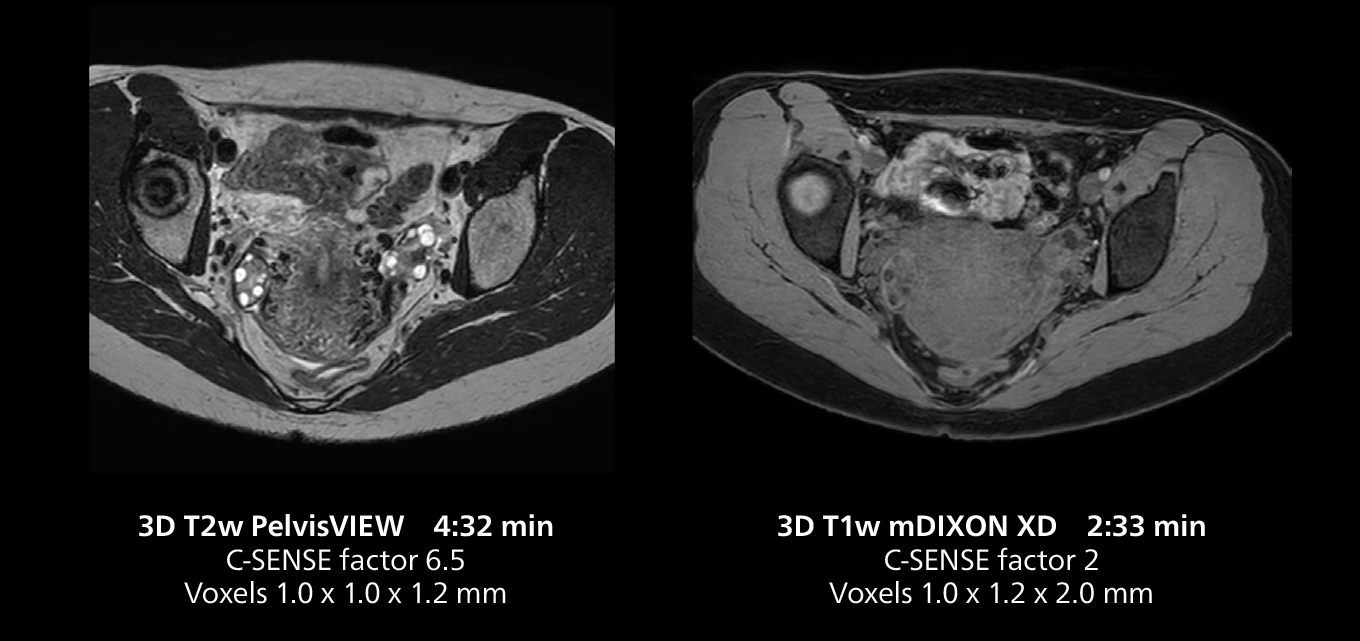

Female pelvis imaging

This MRI case illustrates good resolution and imaging quality obtained within reasonable scan times using the MR 5300 1.5T system with the anterior torso cardiac coil that allows use of a large field of view (FOV).